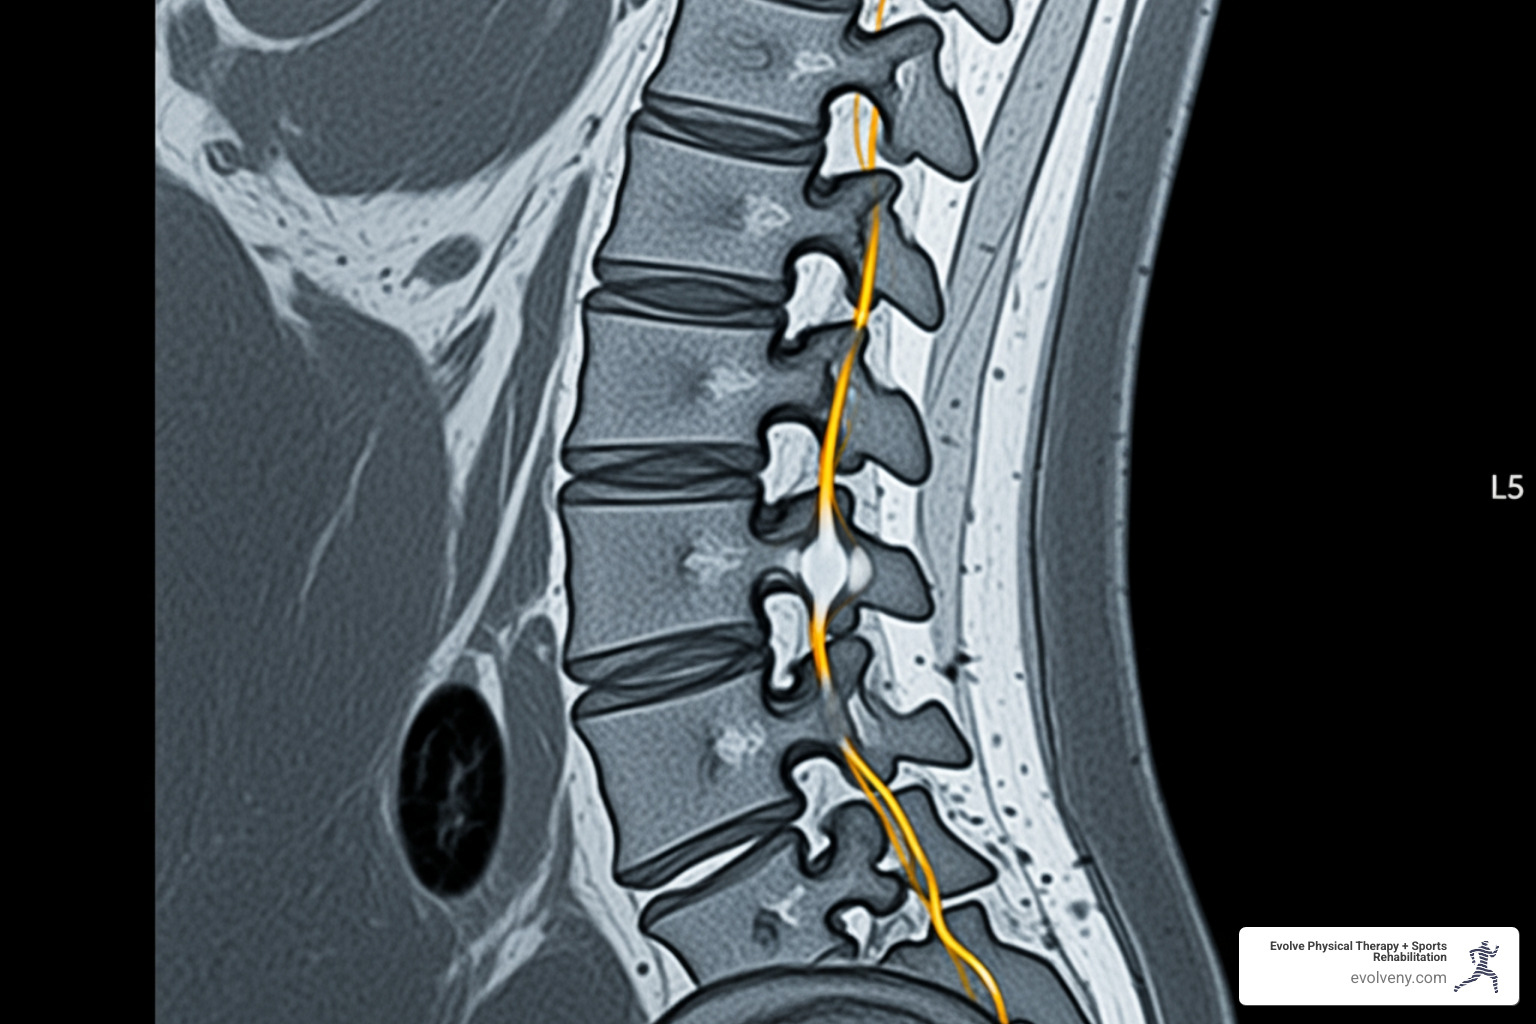

Pain management herniated disc treatment begins with understanding your condition and options. A herniated disc occurs when the soft, gel-like center (nucleus pulposus) of a spinal disc pushes through a crack in its tough outer layer (annulus fibrosus). This can press on nearby nerves, causing pain, numbness, or weakness that radiates down your leg (sciatica) or arm.

Most herniated discs occur in the lumbar spine (lower back), followed by the cervical spine (neck). While the pain can be debilitating, the prognosis is excellent. Over 85% of people improve within 8-12 weeks with conservative treatment, and surgery is rarely needed.

- MRI (Magnetic Resonance Imaging): The gold standard for diagnosing herniated discs. It uses magnetic fields to create detailed images of soft tissues like discs and nerves, showing exactly where compression is occurring.

- CT Scan: Provides cross-sectional images of the spine and is useful for viewing bone structures and discs.

Combining a physical exam with detailed imaging allows your medical team to create the most effective pain management herniated disc strategy for you.